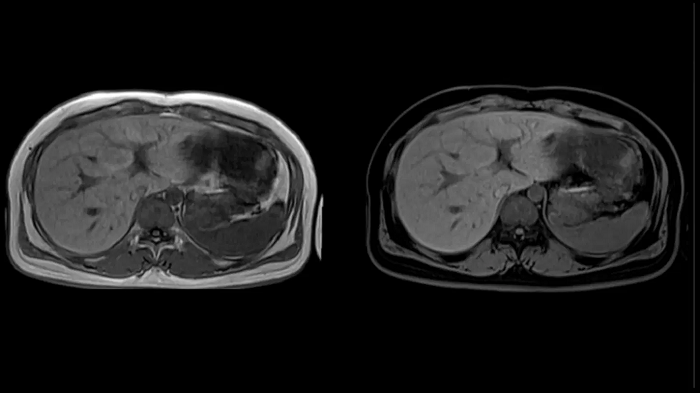

Abdomen

T1 VIBE Dixon with CAIPIRINHA

Get benefitted from Siemens Healthineers dedicated CAIPIRINHA acceleration to gain a complete abdominal volume within a single breath-hold. The Dixon technique offers outstanding fat water separation for a flawless representation of the abdominal anatomy.

MAC-ID: 7aaaa0165. Image Credit: Siemens Healthineers